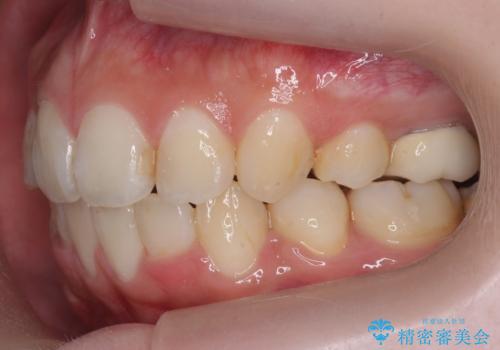

- 前歯のがたつきを主訴に来院。

顔が小さく、顎に大きな歯が入りきらない状態でした。

抜歯してワイヤー矯正を行いました。